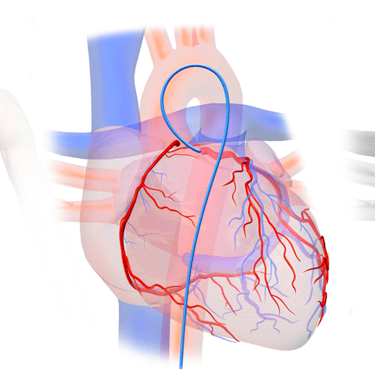

Coronary Angiography / कोरोनरी एंजियोग्राफी

A test to detect blockages in heart arteries using dye and X-ray.

Procedure to open blocked arteries and restore blood flow using balloon and stent.

Coronary Angioplasty (PTCA) / कोरोनरी एंजियोप्लास्टी